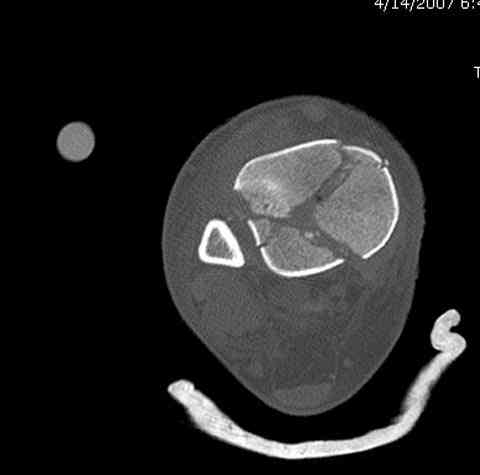

Дополнительные ренгенограммы после дистракции и

обязательная комьютерная томография дают возможности разузнать топографию расположения фрагментов, что немаловажно для планирования хирургического доступа.

По апексу фрагмента ориентируется при планировании

фиксации, также предоперационно определяется

направление фиксирующего материала: шурупа или спицы с упорной площадкой.

Здесь выставлена пара случаев перелома пилона, оба

случая леченные этапным наружным фиксатором.